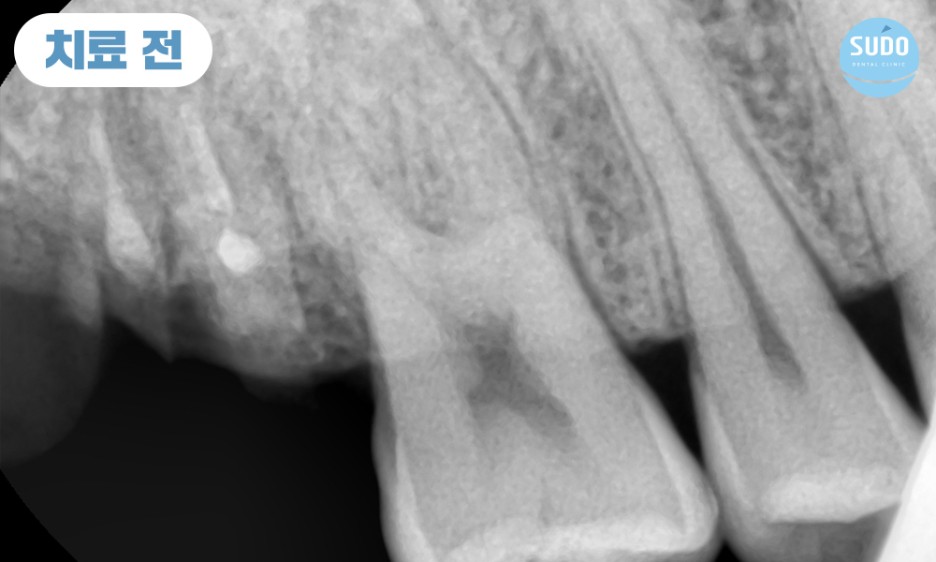

위 환자분은 20대 후반의 남성분으로, 오른쪽 위 가장 안쪽 어금니 보철물이 빠질 것 같다고 하시며 수도치과로 내원해 주셨습니다. 보철물이 완전히 부러진 상태는 아니라서 기존 보철물을 제거한 후 치아 내부 상태를 확인하였습니다.

상태가 양호하다면 부족한 부분을 보강하기 위해 기둥을 세우고 재보철치료를 진행할 수 있었으나, 내부 상태가 좋지 않을 경우 치아를 발치하고 임플란트 치료를 진행해야 할 것으로 설명드렸습니다.

기존의 보철물 제거하고 보니, 이미 뿌리까지 충치가 많이 진행된 상태로 살려서 쓰기 힘들 것이라 판단되어 당일 발치 후 임플란트 진행 계획을 수립하였습니다.

이전 진료 당시에 신경치료를 완료한 후 보철물을 부착한 상태였으므로 충치가 심하게 진행되었음에도 통증을 전혀 느낄 수 없었습니다.